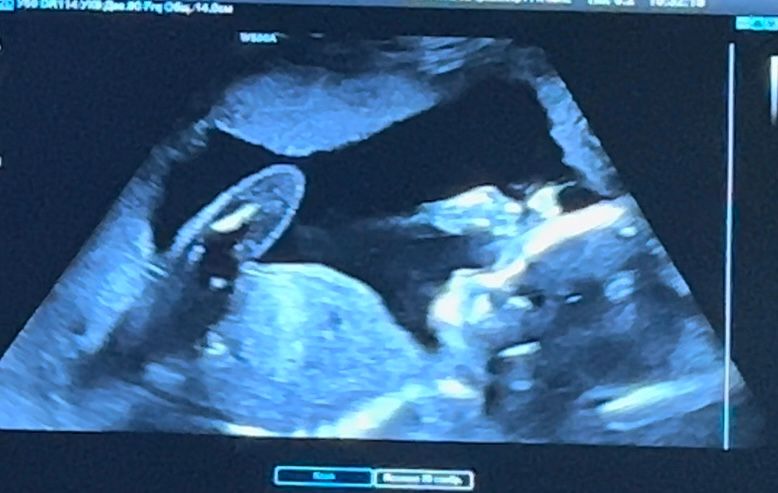

Сняла весь процесс узи с экрана на телефон, и на наиболее понятном стоп-кадре по-моему вижу прям такое серьезное личико с широко распахнутыми блестящими глазками - кто разбирается, это так? (фотку прикреплю)